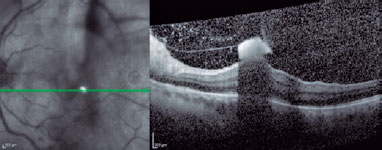

The best-corrected visual acuity (BCVA) was 20/20 in the right eye (RE) and only light perception in the LE. Biomicroscopy revealed anterior vitreous cells in the LE. Fundoscopy showed small, fluffy, creamy white lesions in the posterior pole in the LE. Spectral-domain optical coherence tomography (SD-OCT) images showed vitreous cells, hyaloid thickness with hyperreflective aggregates, and a round-shaped hyperreflective lesion in the inner retinal layers with a shadow effect in the macular area (Figure 1). The ophthalmic examination of the RE was unremarkable.

The clinical and OCT findings were compatible with endogenous fungal endophthalmitis, and the patient was treated with fluconazole 900 mg orally per day. Despite systemic treatment, the lesions progressed (Figure 2), and the patient underwent pars plana vitrectomy (PPV), which resulted in the total resolution of the inflammation. Direct examination and vitreous culture were negative.

Her final BCVA was 20/20 in the RE and counting fingers in the LE. Two months postoperatively, SD-OCT images showed a hyperreflective area caused by the thickening of the inner retinal layers and anatomical distortion of the macula. The poor visual prognosis was related to macular involvement.